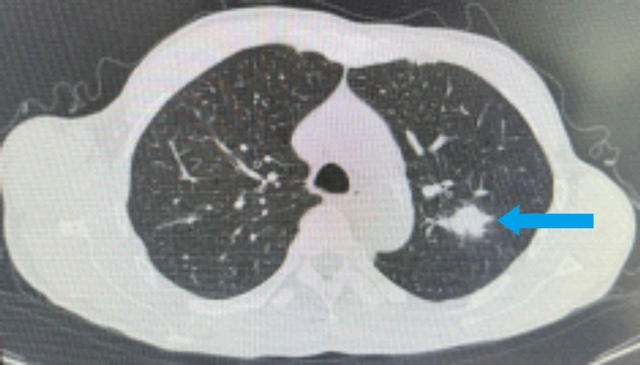

肺部CT:左肺上叶尖后段软组织结节,大小约2.1×1.9cm²,边缘见毛刺,结合病史,考虑肺转移可能。

综合检查结果,西医诊断为:鼻咽部恶性肿瘤(分化型非角化性癌)侵及口咽、咽旁间隙伴咽后、颈部转移淋巴结;肺继发恶性肿瘤;中医诊断为鼻咽癌(痰瘀互结)。